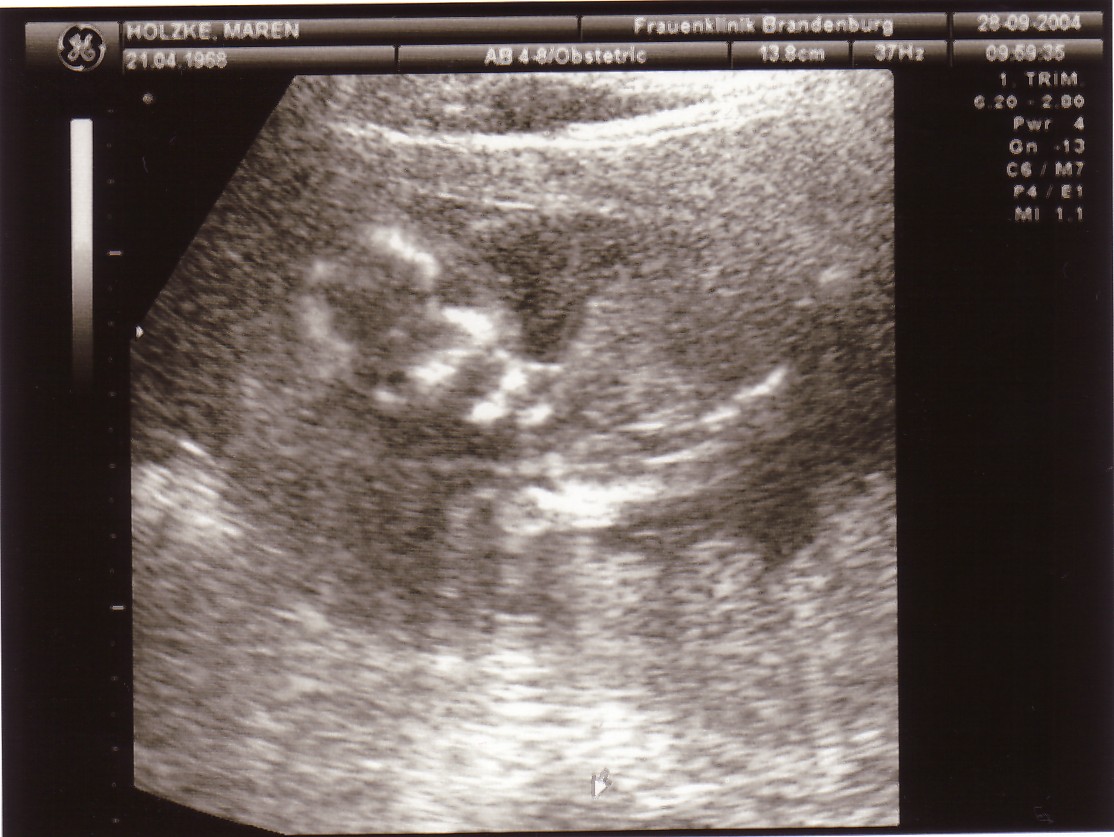

nur kurzer bericht von gestern: alles gut gegangen, bin seit heute offiziell mit BV zu hause. mutter und kind sind wohlauf, herzschlag ist da, krümel bewegt sich ganz normal und ist grade jetzt wieder mal ein kleiner schumi, schön immer mit dem kopf gegen die rechte bauchdecke.

so, und damit du mal weißt, waschbärchen, was auf dich zukommt und so als motivation für die kommenden wochen - da sollst du nemlich auch mal hin, hier das gestrige foto des tages!

krümel 16+3.jpg

krümel klein schumi 16+3

Biene Maja, hab grad dein Foto angeschaut, aber den "kleinen Unterschied" noch nicht gesehen... :wink: habt ihr schon Namen in der engeren Auswahl? Wir sind ja auch schon wieder beim Namensstreit... :wink: , obwohl ja noch überhaupt nichts aktuell ist. Aber man kann ja schon mal ein wenig träumen. 8)